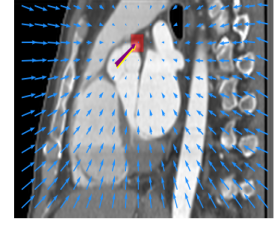

Finally, the proposed network was evaluated for the detection of five additional landmarks: the left coronary ostium, the bifurcation of the LM into the LAD and the LCx, and the origin of the left, non-coronary, and right aortic valve commissures (see Fig. 2). Fig 3 shows vector fields visualizing the predicted displacement vectors in three viewing planes in an image from the test set (for more results, see Appendix). Table 3 lists the Euclidean distance errors between the predicted landmark locations and the reference landmark locations. In addition, box-and-whiskers plots are shown in Fig 4. The best results were obtained for the origin of the right aortic valve commissure. Detection of the origin of the left aortic valve had the most narrow distribution. Outliers were seen during detection of the right ostium, the bifurcation of the LM, and the origin of the non-coronary, and the left aortic valve commissure.

Refer to caption Refer to caption Refer to caption

Figure 3: Vector fields visualizing the predicted displacement vectors in the axial, coronal, and sagittal plane in an image from the test set where detection of the right coronary ostium was performed. The magnitudes of the vectors should point at the right ostium, but they are rescaled for visualization purposes. The red squares indicate posterior probabilities larger than 0.5, obtained by the classification network for image patches. Reference and computed landmark annotations are indicated with a yellow and purple arrow, respectively.